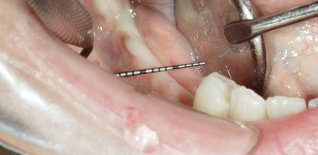

Mancanza dei denti postero inferiori di destra in assenza di osso sufficiente per poter posizionare degli impianti (spessore osso residuo meno di 2 mm).

Eseguito innesto d'osso in blocco e dopo circa 4 mesi inserzione degli impianti.